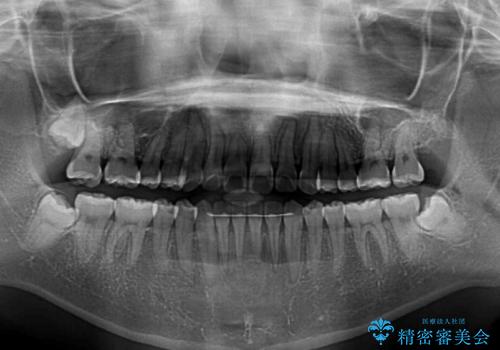

- 前歯の捻れと、ちょっとした出っ張りを気にして来院された患者様です。

歯と歯の間を削る(IPR)ことでデコボコを解消し、インビザラインで整えることとしました。

インビザライン治療特有の奥歯が接触しない時期が続き、当初予定よりも期間がかかりましたが、最終的には安定した咬み合わせと、整った前歯になりました。